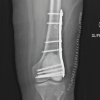

The patient’s wrist was immobilized in a below-elbow plaster slab for 4 weeks and then transitioned to a splint/brace. Early finger motion was encouraged from day 1. Gentle wrist mobilization was started at 7 weeks after removal of the K-wires, followed by progressive ROM and grip strengthening thereafter. The patient resumed his job as a driver at 3 months post-operatively. At 12 months after the surgery, the patient reported minimal discomfort with activities of daily living, no night pain, and no sensory complaints. He was able to bear weight on his wrist and perform his job as a driver without limitations. The surgical wound was well healed and there was no mass or localized warmth. Final ranges of motion were good (Fig. 3), with 50° dorsiflexion, 40° palmar flexion, 90° pronation, and 90° supination.

Figure 3: Post-operative clinical images with wrist range of motion (left); antero-posterior wrist radiograph taken at 12 months post-operatively (right).

Grip strength as a percentage of that of the healthy side was 80–85%, Mayo Wrist Score was 85 (Good), and disabilities of the arm, shoulder, and hand score was 8.3. VAS score was 1–2/10, but only during exertion. Surveillance imaging at 12 months follow-up showed maintained carpal alignment and good graft incorporation, with some relatively lucent areas in the middle of the iliac crest graft (Fig. 3). A Fluorodeoxyglucose positron emission tomography-computed tomography was done at this stage to rule out local recurrence, and it turned out to be negative for the same and also for distant metastasis.